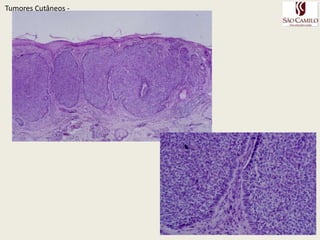

TumoresCutâneos - Tumores Cutâneos Malignos da Pele

TumoresCutâneos - CâncerCutâneoNão Melanoma  Carcinoma Basocelular - CBC

Carcinoma Espinocelular – CEC